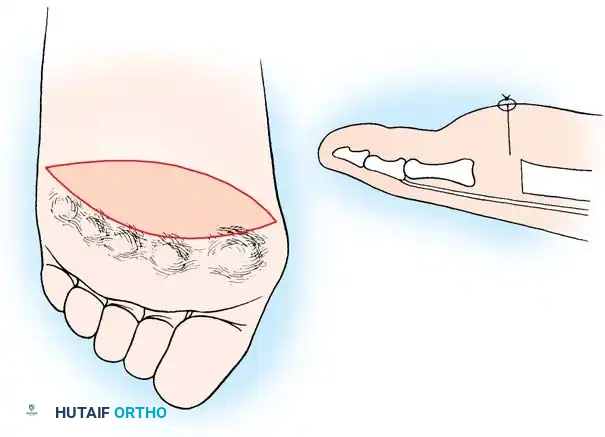

- Approach: Two dorsal longitudinal incisions are typically utilized (one centered between the 2nd and 3rd rays, and one between the 4th and 5th rays) to access all lesser MTP joints while preserving dorsal skin bridges. Alternatively, a transverse plantar approach can be used if severe plantar callosities require excision.

- Resection: The extensor tendons are retracted or lengthened (Z-plasty). The dorsal capsule is opened, and the collateral ligaments are sharply divided to allow plantarflexion of the metatarsal.

- Osteotomy: An oscillating saw is used to resect the metatarsal heads at the anatomical neck. It is imperative to create a smooth, parabolic cascade (the 2nd metatarsal should be the longest, tapering down to the 5th).

- Soft Tissue Balancing: The plantar plate and fat pad, which have migrated distally, are mobilized and pulled proximally under the remaining metatarsal stumps. If the toes remain contracted, closed osteoclasis or PIP joint resection arthroplasties may be performed.

- Pinning: Smooth Kirschner wires (K-wires) are driven antegrade through the toes and retrograde into the metatarsal shafts to hold the toes in neutral alignment.

Intraoperative view demonstrating the exposure and resection of the lesser metatarsal heads to decompress the forefoot and allow reduction of the dislocated digits.